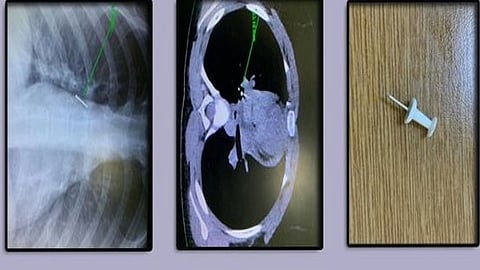

نجح فريق طبي بمستشفى الأمير متعب بن عبدالعزيز في سكاكا بمنطقة الجوف، من إنقاذ طفلة في حالة نادرة وقعت لها؛ حيث قامت وعن طريق الخطأ باستنشاق دبوس ليستقر في القصبة الهوائية.

وأوضحت صحة الجوف، عبر تويتر، أن الطفلة وصلت إلى قسم الطوارئ بالمستشفى، وكانت، عن طريق الخطأ،خج قد استنشقت دبوسًا ليستقر في القصبة الهوائية اليمنى داخل رئة الطفلة.

وأضافت أن الطفلة تم استقبالها محولة من أحد مستشفيات المنطقة إلى مستشفى الأمير متعب بن عبدالعزيز، ليتمكن الفريق الطبي بقسم جراحة الصدر، وبعد القيام بالفحوصات المخبرية والاشعاعية اللازمة، من إجراء العملية بنجاح.

وأشارت صحة الجوف إلى أن العملية تمت باستخدام المنظار القصبي وبشكل دقيق؛ حيث تم استخراج الجسم الغريب، موضحة أن حالة الطفلة الصحية مستقرة.